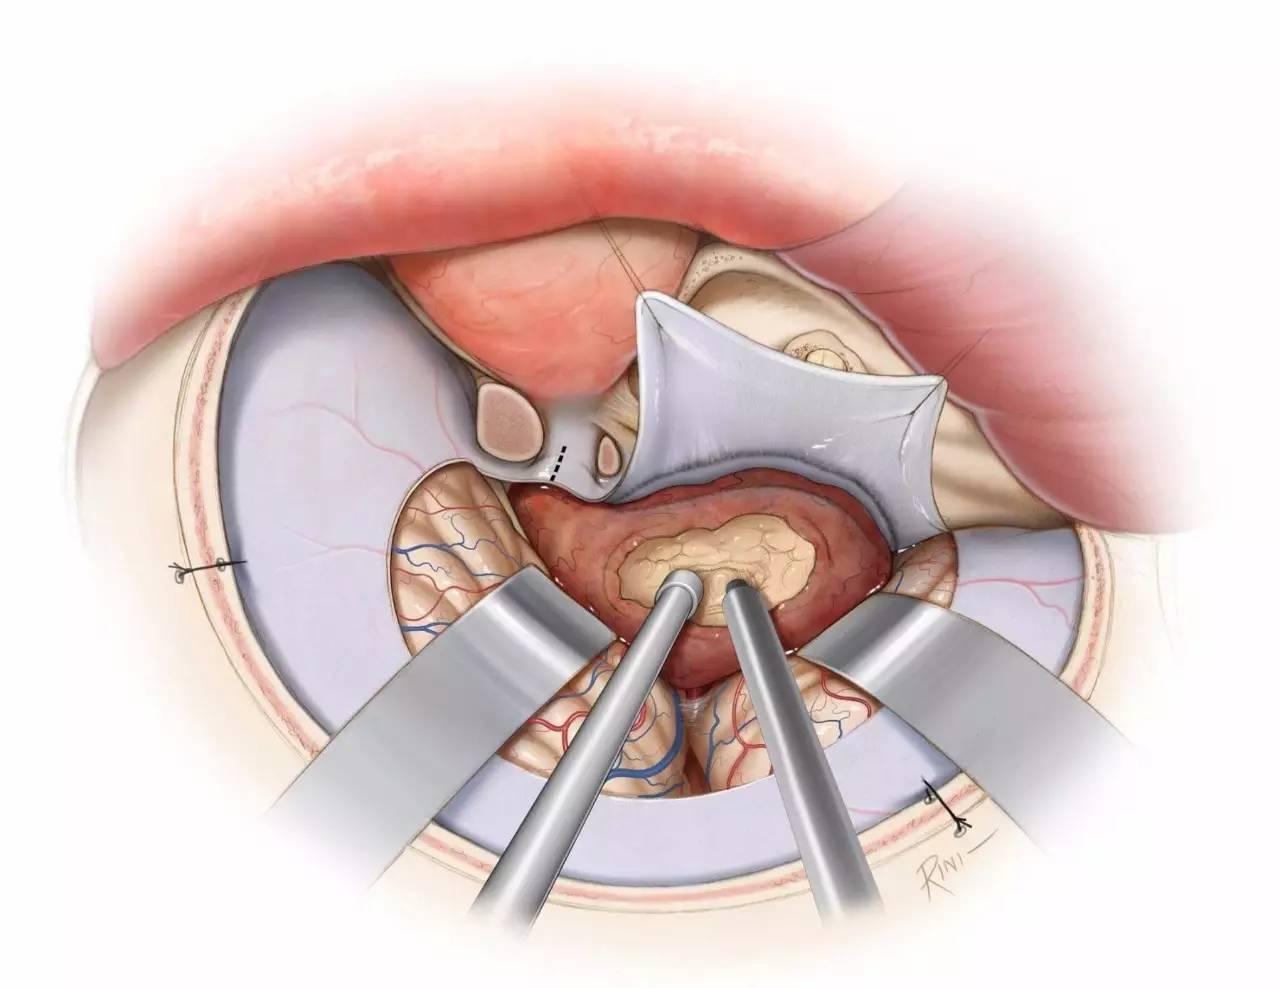

图2:逐层分步解剖右侧海绵窦。海绵窦外侧壁内走行有动眼神经、滑车神经、三叉神经眼支和上颌支(Rhoton教授原图认为上颌支位于海绵窦以外,译者注),外展神经则紧贴颈内动脉行于海绵窦内部(左上图)。剥开覆盖颞叶的外层脑膜层(即海绵窦外侧壁的外层,译者注),可见动眼神经和滑车神经进入海绵窦顶壁,并前行进入眶上裂(右上图)。动眼神经在海绵窦顶壁行于一小段蛛网膜池中(红色箭头),直至前床突下缘时才进入海绵窦侧壁(黄色箭头,左中图)。剥除海绵窦外侧壁的残余硬膜(外侧壁的内层,译者注)(右中图)。三叉神经后根已被翻向前方,以显露海绵窦下界的后部(黄色箭头),位于岩尖三叉神经压迹的内侧(左下图)。向前翻开三叉神经主干及全部三分支,显露海绵窦的静脉间隙(右下图)。(感谢Rhoton教授对图片的授权)

图3:硬膜外入路行右侧海绵窦的手术学解剖。颞前-眶颧开颅及硬膜外前床突切除术已完成,眶上裂的外侧缘已显露(左上图,此时硬膜外前床突切除术其实尚未完成,译者注)。在眶上裂的外侧缘处切断额颞或脑膜眶硬膜返折,将海绵窦外侧壁的外层从内层上剥离。因此,掀开海绵窦外侧壁的外层(脑膜层),即可显露融入外侧壁内层的颅神经(右上图)。

切断脑膜中动脉,继续向后内侧剥离硬膜,即可暴露岩浅大神经,其通常行于岩骨段颈内动脉上方,故可作为其定位标志。沿中颅窝剥离硬膜的内侧界为前岩床突硬膜返折,后界为岩骨嵴(左中图)。床突旁区域的放大观(右中图)。注意,经Parkinson三角进入硬膜内是可能的(译者认为是“海绵窦内、硬膜间”,译者注)。进一步剥除海绵窦外侧壁的内层(左下图)。病灶经外侧壁侵犯海绵窦的通道也即为手术进入海绵窦的径路。此时可见以下中颅窝三角:前内侧三角(三叉神经眼支和上颌支之间)、前外侧三角(三叉神经上颌支和下颌支之间)、后外侧三角(即Glasscock三角,三叉神经下颌支和岩浅大神经之间)、后内侧三角(即Kawase三角,三叉神经下颌支外侧与岩浅大神经后方区域)。最后一图展示了去除中颅窝底和内听道顶壁部分骨质后的解剖(右下图)。(感谢Rhoton教授对图片的授权)

图4:海绵窦区的硬膜内入路解剖。大型肿瘤应联合硬膜内及硬膜外入路。(感谢Rhoton教授对图片的授权)